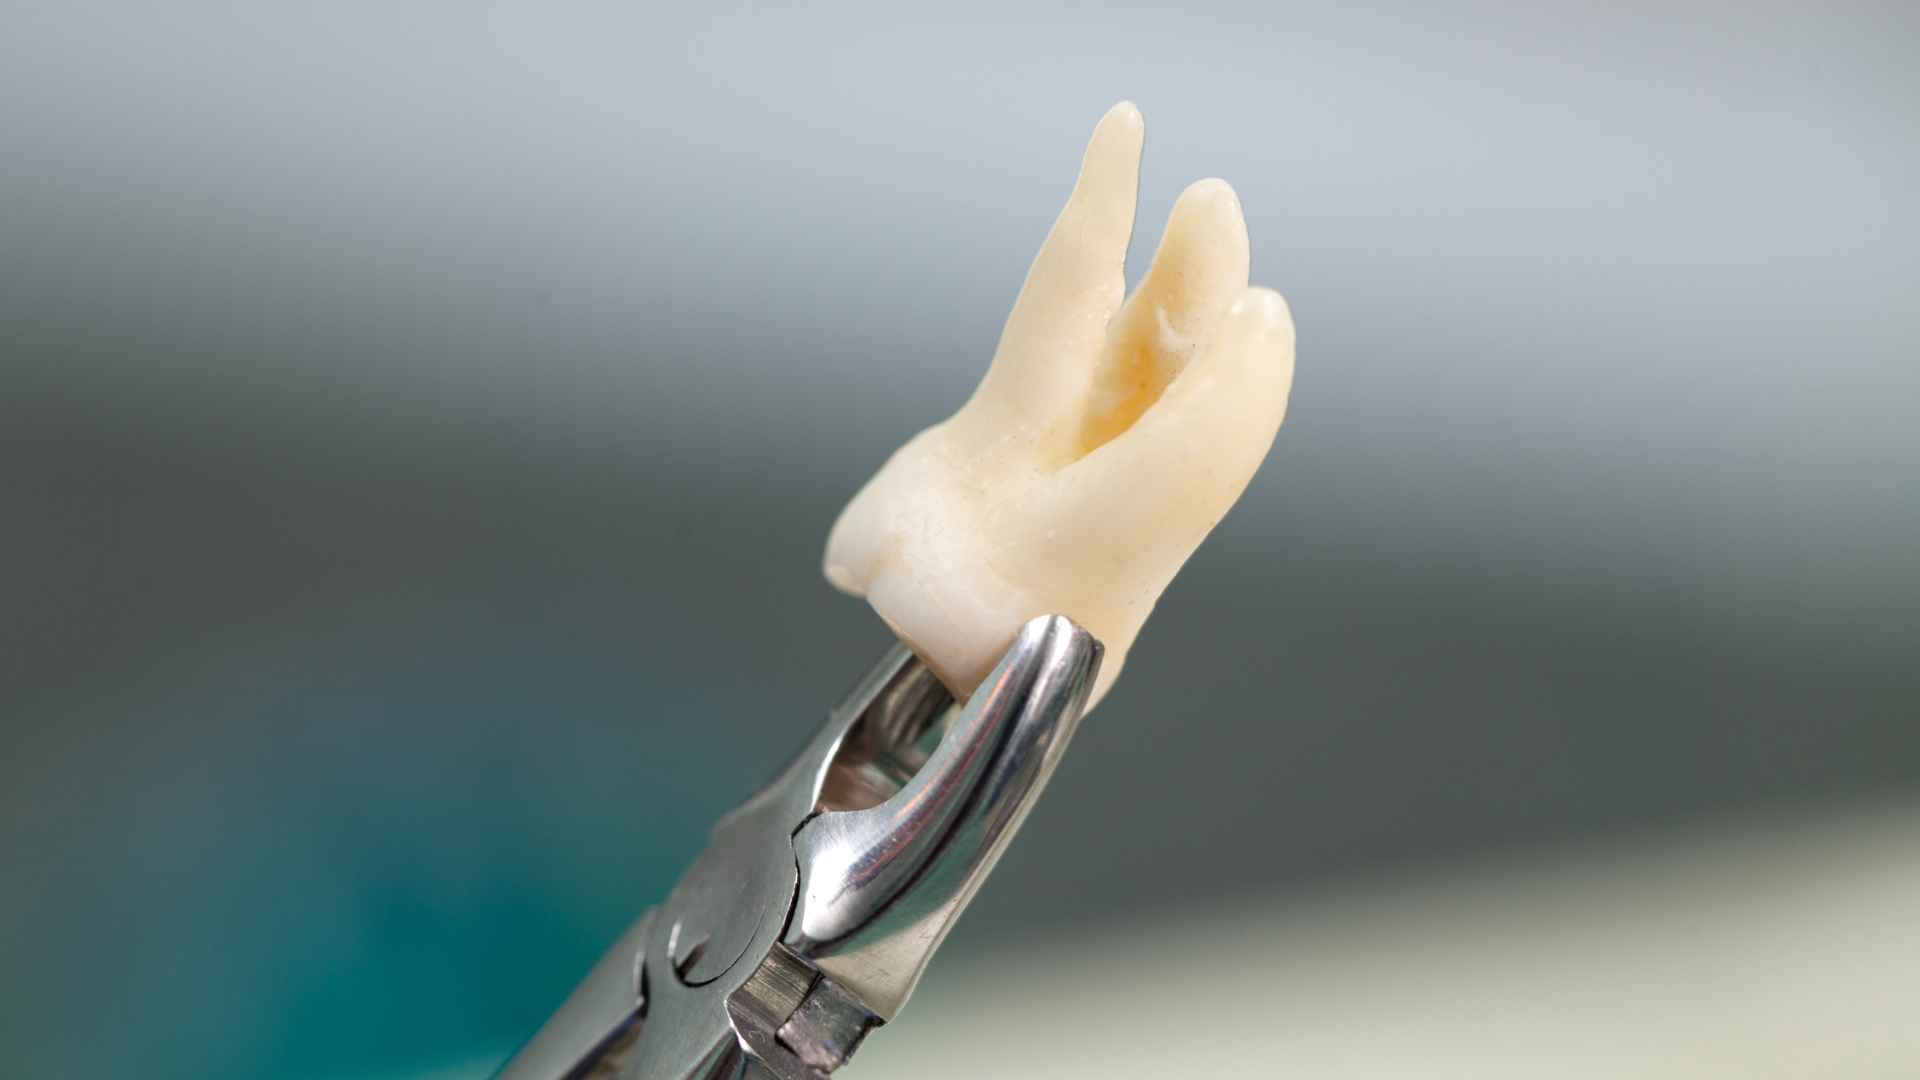

• ทันตแพทย์จะทำการถอนฟันคุดอย่างระมัดระวัง เพื่อลดความเสียหายต่อเนื้อเยื่อรอบข้าง